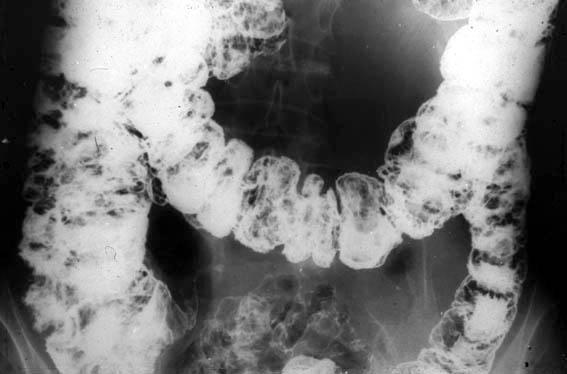

Sindrome de Cronkhite-Canada que mostró gastroenteritis perdedora de proteínas (caso reportado en forma conjunta por los Drs. Sakita y Fukutomi, el año 1966, Centro Nacional del Cáncer)

Tokyo Pref., Centro Nacional de curaciones de Cáncer, Hospital Central y Centro Kyusyu de Curaciones de Cáncerc (国立がんセンター中央病院, Dr.崎田, 福富)

Lesión que asemeja tumoración/Sindrome de Cronkhite-Canada

colon/lesión que abarca dos o más regiones del colon

Rayos X

20 - 24